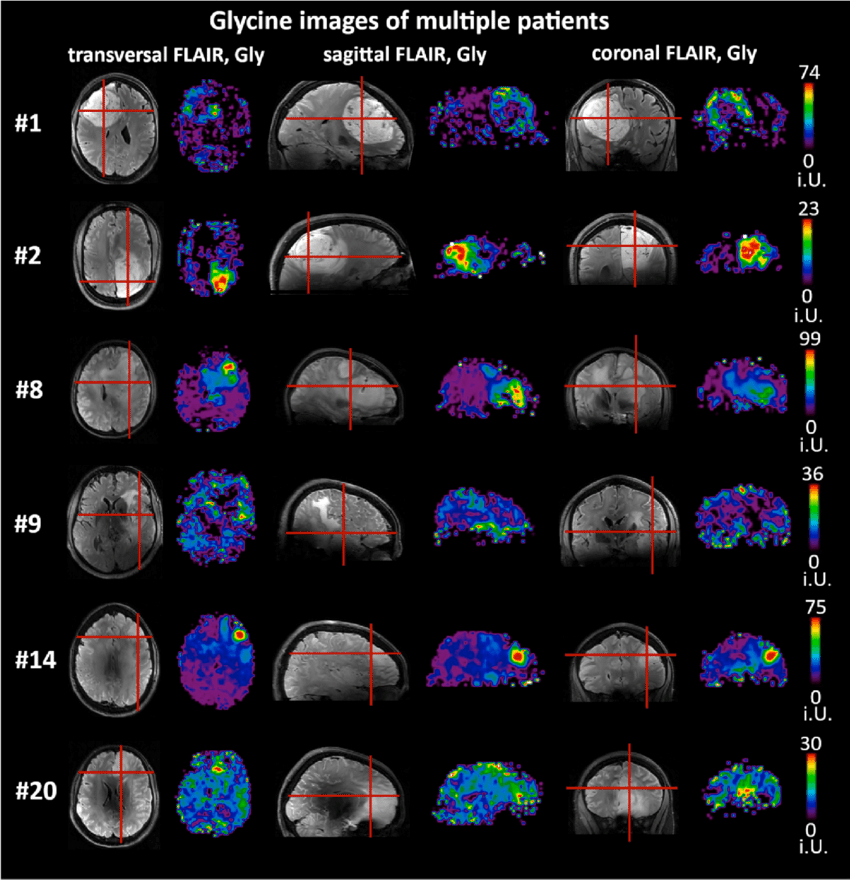

Glycine: What The Heck is That!

Brain Science:

Our last blog was about the possibility of using psychedelic drugs as a future treatment. In this one we look at glycine. Scientists have recently discovered that a common amino acid, glycine, can deliver a "slow-down" signal to the brain, likely contributing to major depression, anxiety and other mood disorders in some people. The discovery, improves understanding of the biological causes of major depression and could accelerate efforts to develop new, faster-acting medications for such hard-to-treat mood disorders.

Like our discussion on Psychedelics, the key to this discovery was being able to understand how brain cells receive and transmit signals into other brain cells. You may remember that we have proteins (neurotransmitters), or chemical substances that either inhibit signal transfer or we have substances that accelerate signal transfer. With psychedelics we have identified the fact that certain receptors are enhanced by the drugs. We also discovered that Glycine has a similar effect. It exists in a natural form in the brain as a neurotransmitter and therefore aides or deters signal transfer. . As recently as last month, scientists have reported that within glycine we have identified the specific protein receptor that accelerates the depression reaction. The newly discovered receptor, for what it's worth, it is called GPR158. They have further discovered that if that protein (glycine) is lacking in that certain receptor gene (GPR158) that nerve area was surprisingly resilient to chronic stress. What they have now discovered is that the receptor combined with another proteine actually becomes an inhibitor. So research is now going on to regulate the glycine by therapeutically controlling the degree of inhibiting and accelerating the glycine in cells specific to depression. ( Originally it was thought there are only about 20 ,that has been adjusted to just one.) So studies are now around how to do this. More research is needed to understand how the body maintains the right balance of mGlyR receptors (brain cells with glycine as the neurotransmitter) and how brain cell activity in the aggregate is affected. Last months discovery found a protein that can attach to the glycine protein like a clamp and turn it into a inhibitor of the cell signal, in effect turning off the depression related brain cells.